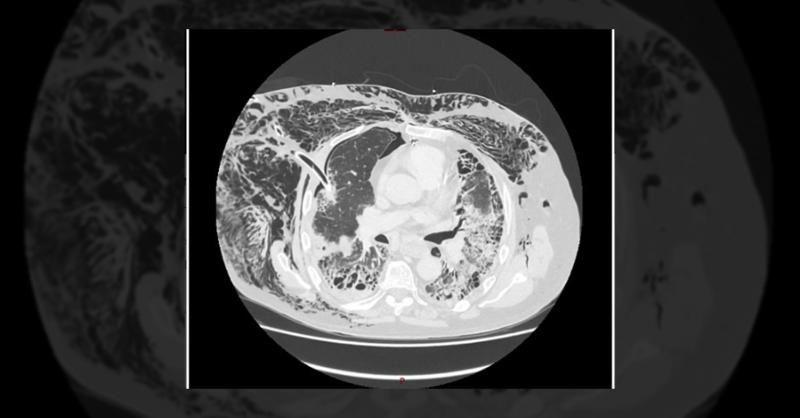

- Management of an Elderly Patient with Chest Drain Malposition

A 78-year-old male, with a complex medical history involving tobacco use, elevated BMI, asbestos exposure, and advanced pulmonary fibrosis, presented with debilitating shortness of breath. Notably, he had a history of left video-assisted thoracoscopic bullectomy and talc pleurodesis due to a previous pneumothorax. Despite a recent course of antibio

Management of an Elderly Patient with Chest Drain Malposition